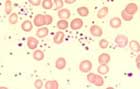

Die Thrombozyten betragen >450 x109/L, können aber auch Werte weit über 1000 x 109/L erreichen. Das mittlere Thrombozytenvolumen ist oft vergrössert, mit Thrombozytenanisozytose und Riesenplättchen sowie hypo- oder agranulären Formen. Gelegentlich finden sich Megakaryozytenkernreste. Eine Basophilie ist typisch, aber kaum sehr ausgeprägt. Eine milde Leukozytose bis maximal 20 x109/L kann vorkommen, höhere Werte sprechen gegen die Diagnose einer ET.